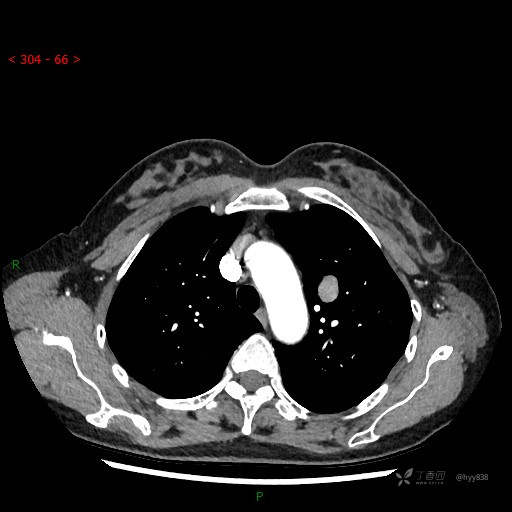

增强动脉期